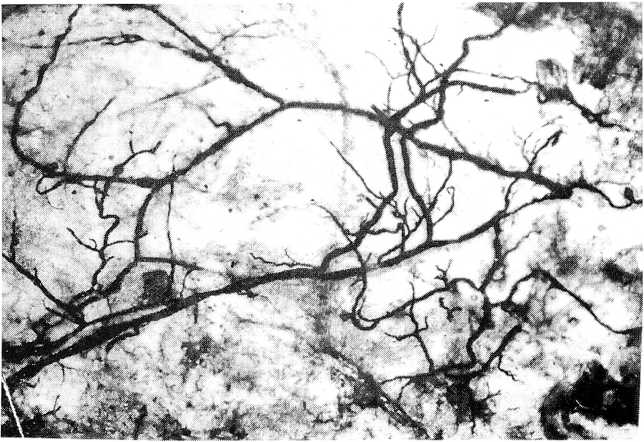

Рис. 3. Просветленный препарат подвздошной мышцы с крупными венами, заполненными массой Герота-Акиловой (увеличение в 10 раз)

В подвздошной фасции среди вен, окрашенных красящей массой, преобладали сосуды, мелкие по калибру. Они представляли густую сеть мелких венозных стволов, занимающих почти всю поверхность подвздошной фасции (рис. 4).